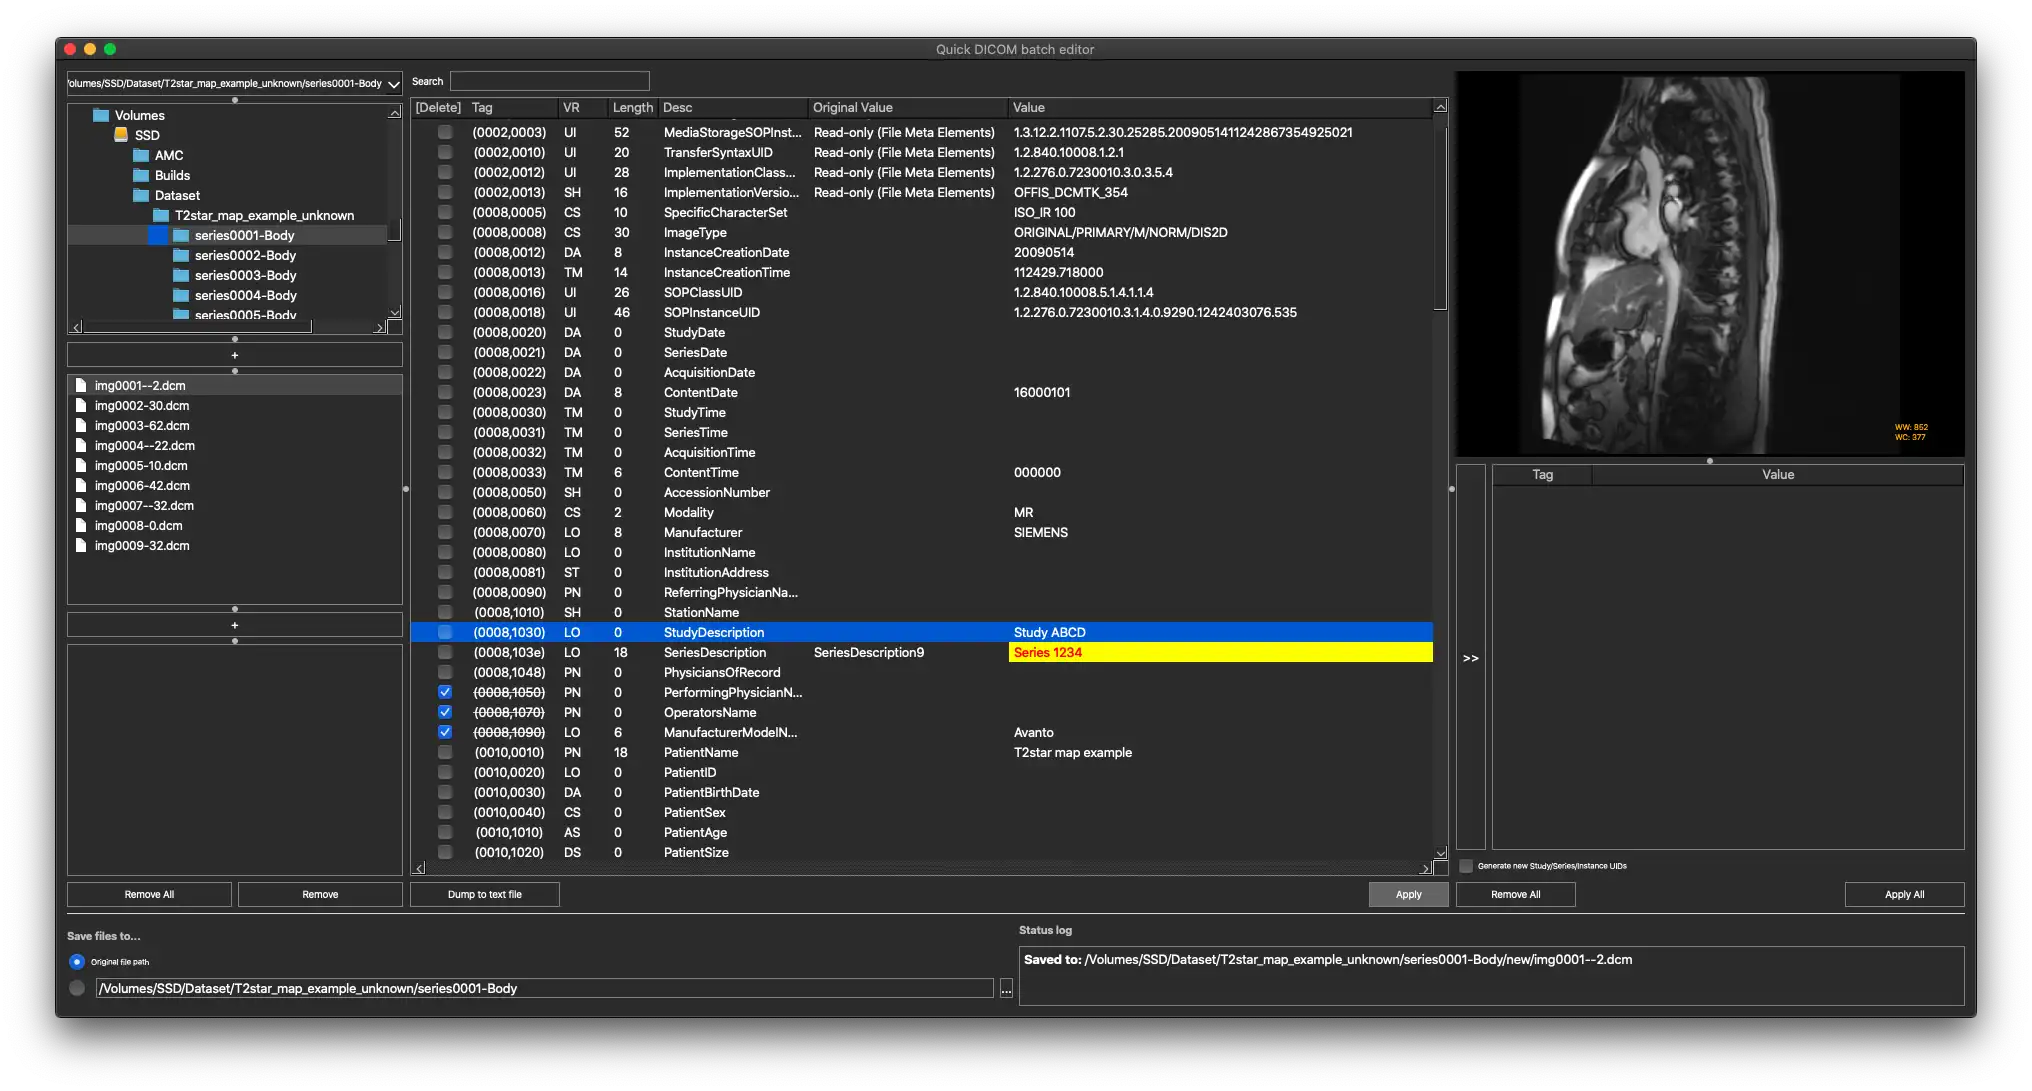

SCREENSHOTS

* Descrição geral

- Ver e modificar tags DICOM de um único arquivo

- Visualize e modifique as tags DICOM de vários arquivos

- Despeje as tags DICOM em um arquivo de texto

- Imagens de visualização (dados de pixel DICOM)

- Visualize e modifique as tags DICOM de um único arquivo

- Visualize e modifique as tags DICOM de vários arquivos

- Despejar tags DICOM em um arquivo de texto

- Imagens de visualização (dados de pixel DICOM)

- Plataforma cruzada - Windows, Mac, Linux